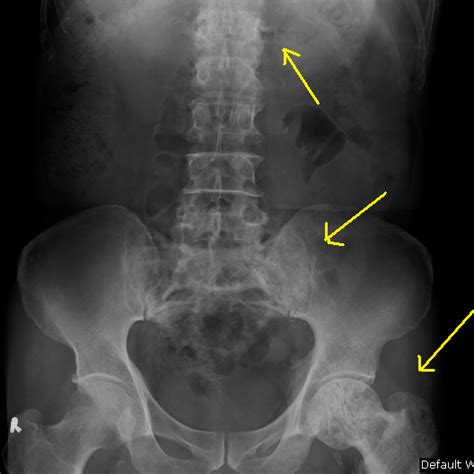

Osteitis deformans sir james paget described paget's disease of bone in 1877. Pain associated with bones and joints, headaches, hearing loss, enlargement or bowing of bones. What are signs and symptoms of paget's disease? The management of paget's disease of the breast. • frequently affects the pelvis, spine, skull and proximal long bones and has. • chronic bone disorder characterized by excessive abnormal bone remodeling. Altman, md, professor of medicine, division of rheumatology and immunology, university of california, los angeles, for assistance in the. Paget's disease is the second most common type of bone disease after osteoporosis.

• frequently affects the pelvis, spine, skull and proximal long bones and has.